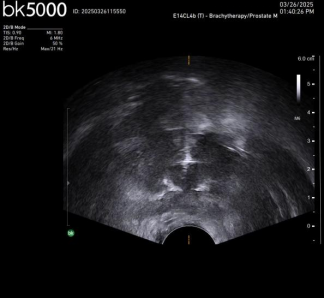

Case2. 超声定位电针穿刺及消融后改变